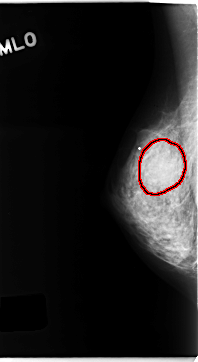

Digital Database for Screening Mammography

Volume: cancer_05 Case: C-0154-1

C_0154_1.RIGHT_MLO

RIGHT_MLO LINES 4704 PIXELS_PER_LINE 2568 BITS_PER_PIXEL 12 RESOLUTION 50 OVERLAY

FILE: C_0154_1.RIGHT_MLO.OVERLAY

TOTAL_ABNORMALITIES 1

ABNORMALITY 1

LESION_TYPE MASS SHAPE ROUND MARGINS ILL_DEFINED

ASSESSMENT 4

SUBTLETY 3

PATHOLOGY MALIGNANT

TOTAL_OUTLINES 1

BOUNDARY